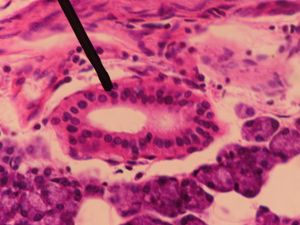

'''끼워넣인관'''(볼관)은 외분비샘에서 샘꽈리에서 줄무늬관으로 직접 연결되는 부분이다. 소엽내관의 일부를 형성하며, 관 시스템 중 가장 얇은 상피를 가진다. 상피는 일반적으로 "낮은" 단순입방상피로 분류된다.[1] 이자[2][3][4]와 침샘[5][6][7] 모두에서 발견된다.

소엽내관은 외분비샘 내의 소엽에 위치하며, 샘꽈리에서 바로 소엽간관(소엽 사이)으로 연결되는 부분이다. 끼임관과 줄무늬관의 두 하위 구획으로 구성된다. 인간의 유선에서 소엽내관은 소엽 내에 위치하는 샘 시스템의 일부이다. 소엽에는 소엽내관에 의해 분비성 샘포가 배출되는 여러 개의 관 묶음이 포함되어 있다. 소엽내관은 일반적으로 근상피세포로 덮인 단층 입방 상피세포로 덮여 있다. 소엽의 소엽내관은 소엽 사이의 소엽간관으로 배출된다. 췌장[14][15][16]과 침샘[17]에서 관찰할 수 있다.

소엽내관(Intralobular duct)은 외분비샘 내의 소엽에 위치하며, 샘꽈리에서 분비된 물질을 소엽간관(소엽 사이)으로 운반하는 관이다. 끼임관과 줄무늬관으로 구성된다.

단순 입방 상피로 둘러싸여 있으며,[1] 췌장[14][15][16]과 침샘[17]에서 관찰할 수 있다.

인간의 유선에서 소엽내관은 소엽 내에 위치하는 샘 시스템의 일부이다. 소엽에는 소엽내관에 의해 분비성 샘포가 배출되는 여러 개의 관 묶음이 포함되어 있다. 소엽내관은 일반적으로 근상피세포로 덮인 단층 입방 상피세포로 덮여 있으며 소엽의 소엽내관은 소엽 사이의 소엽간관으로 배출된다.

3. 1. 1. 끼임관 (Intercalated duct)

'''끼워넣인관'''(intercalated duct) 또는 볼관은 외분비샘에서 샘꽈리에서 줄무늬관으로 직접 연결되는 부분이다.[1] 끼워넣인관은 소엽내관의 일부를 형성한다. 이 관은 관 시스템 중 가장 얇은 상피를 가지며, 상피는 일반적으로 "낮은" 단순입방상피로 분류된다.

이들은 췌장[2][3][4]과 침샘 모두에서 발견된다.[5][6][7]